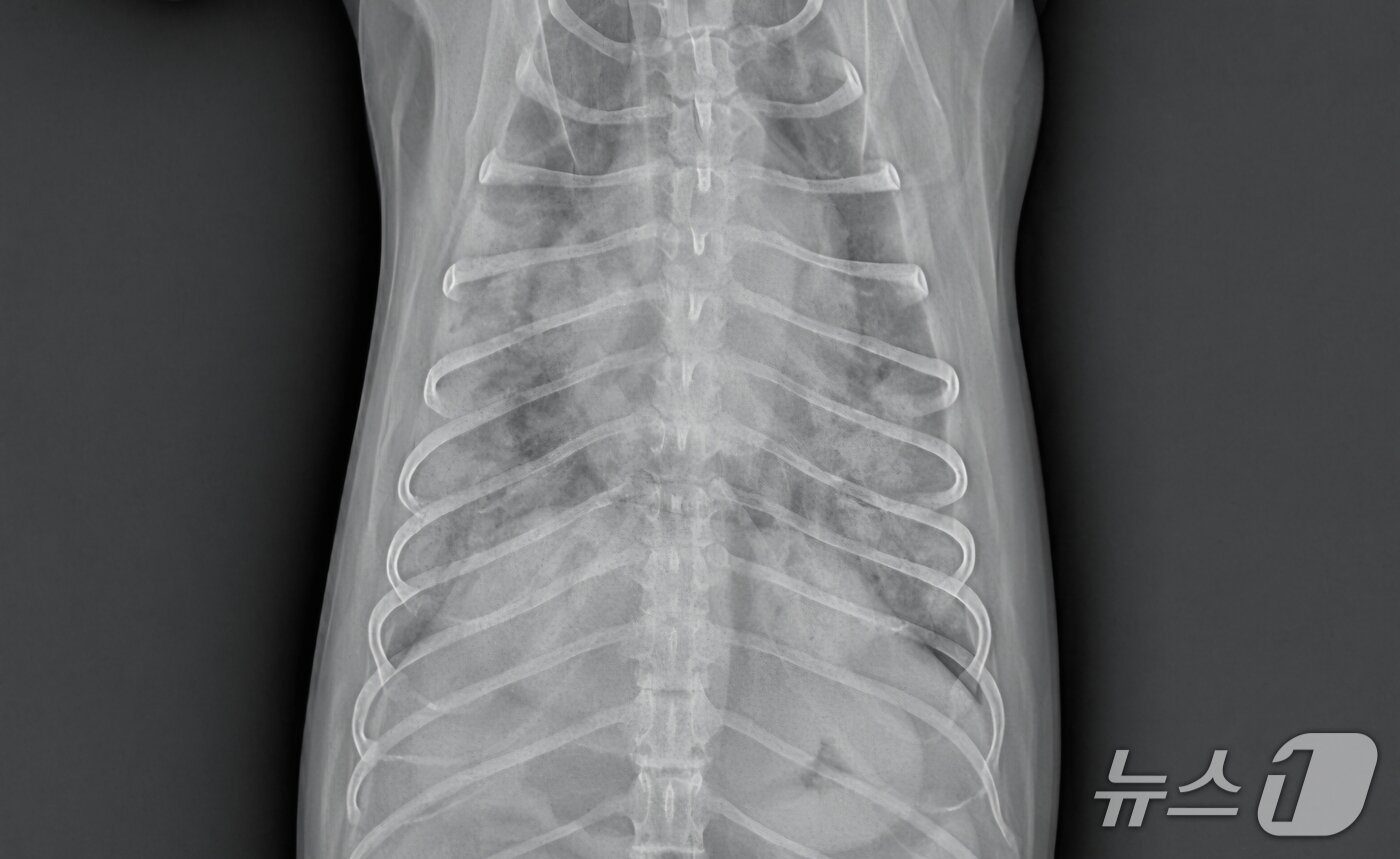

본문 이미지 - 심장에 문제가 있는 반려견 엑스레이 사진(더케어동물의료센터 제공) ⓒ 뉴스1

심장에 문제가 있는 반려견 엑스레이 사진(더케어동물의료센터 제공) ⓒ 뉴스1